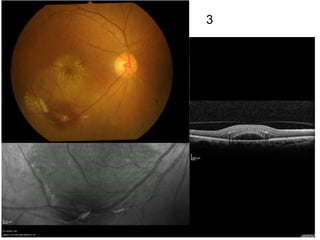

some samples

94

95

96

97

98

99

100

101